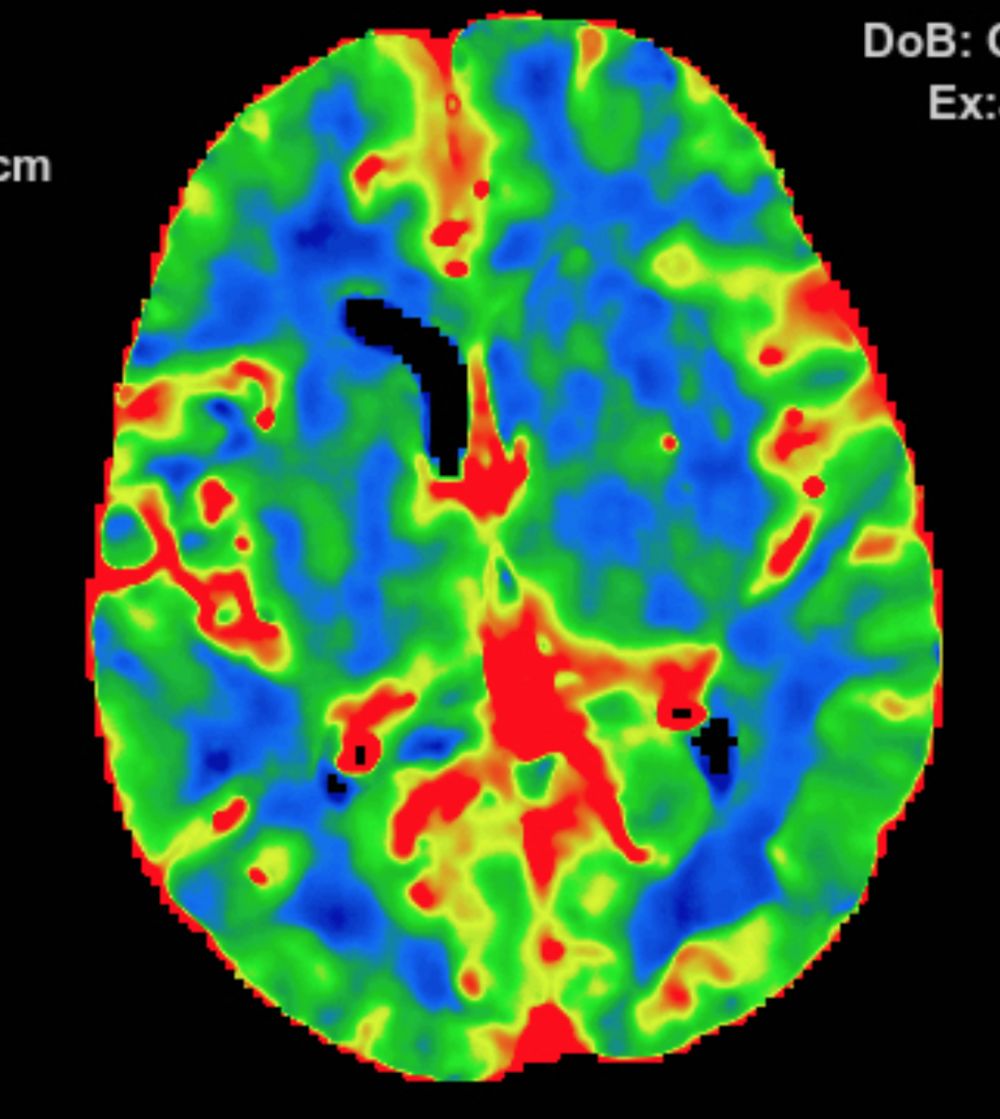

多模式CT影像提示:左侧大脑中动脉M1段闭塞,存在CBF-CBV不匹配。

图3 CTP存在CBF-CBV不匹配

2.手术指征:患者应用阿替普酶溶栓后症状仍持续加重,CTA示左侧大脑中动脉闭塞。CTP存在CBF-CBV不匹配,有介入治疗指征。